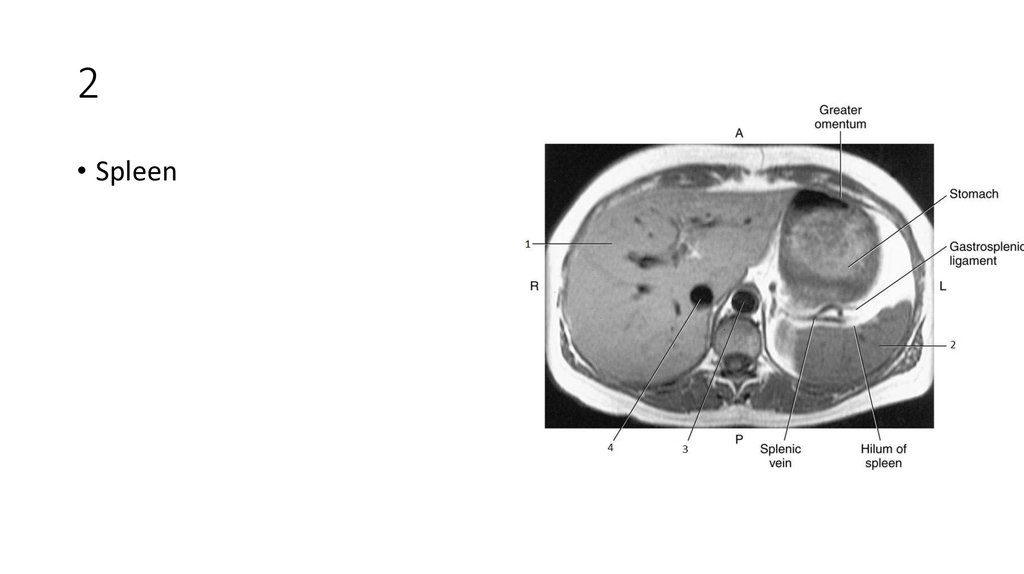

10. 1

• Right Adrenal Gland

11. 1

12. 2

• Spleen

13. 2

14. 3

• Liver

15. 3